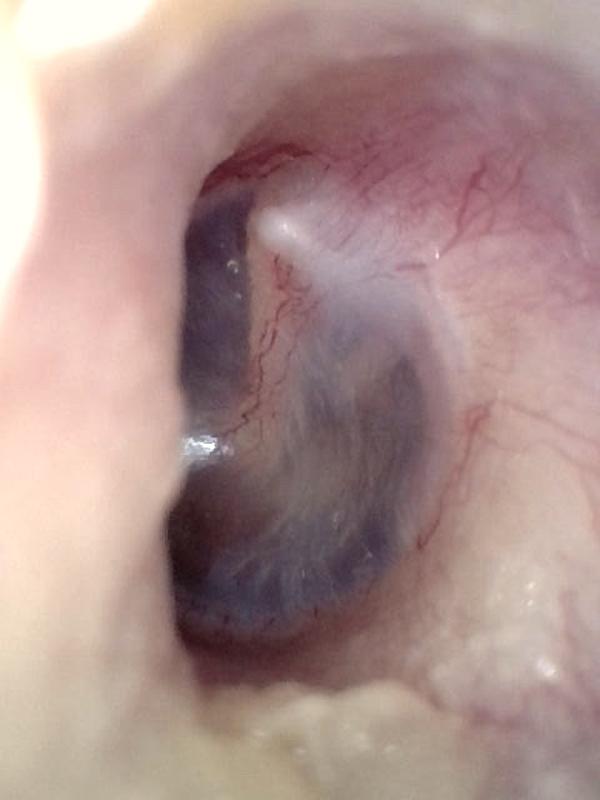

Hemotympanum